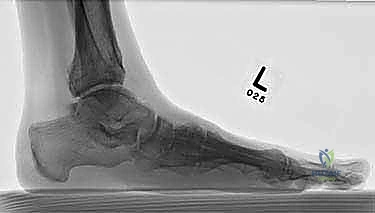

- الأشعة السينية أثناء الوقوف (Weight-bearing X-rays): وهي أهم أداة تشخيصية. الأشعة العادية والسرير فارغ لا تظهر المشكلة الحقيقية؛ يجب التقاط الأشعة والمريض يقف ليتحمل وزن الجسم، مما يظهر الانهيار الفعلي للمفاصل وتضيق المسافات بين العظام.

- الأشعة المقطعية (CT Scan): توفر صوراً ثلاثية الأبعاد للعظام، وهي ضرورية جداً للتخطيط الجراحي الدقيق وتحديد مدى التلف العظمي والزوايا المطلوبة للتثبيت.